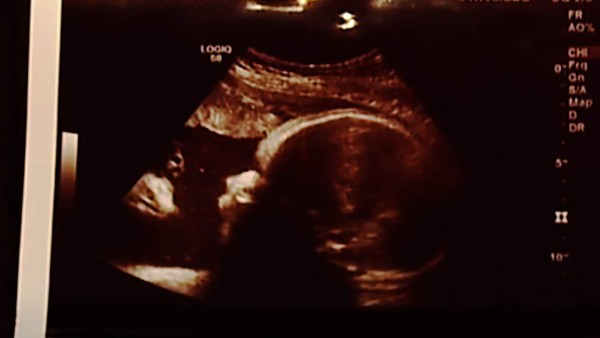

La imagen muestra al bebé con una una lo que parece ser la figura de un hombre con barba y pelo largo que se asemeja mucho a la imagen que nos hemos formado de la apriencia física de Jesús.

Los padres que esperan al bebé dicen no ser muy religiosos pero que claramente ven la imagen de Jesús con la corona de espinas mirando a su hijo y les emociona mucho.

¿Es la imagen de Jesús lo que aparece en el ultrasonido?